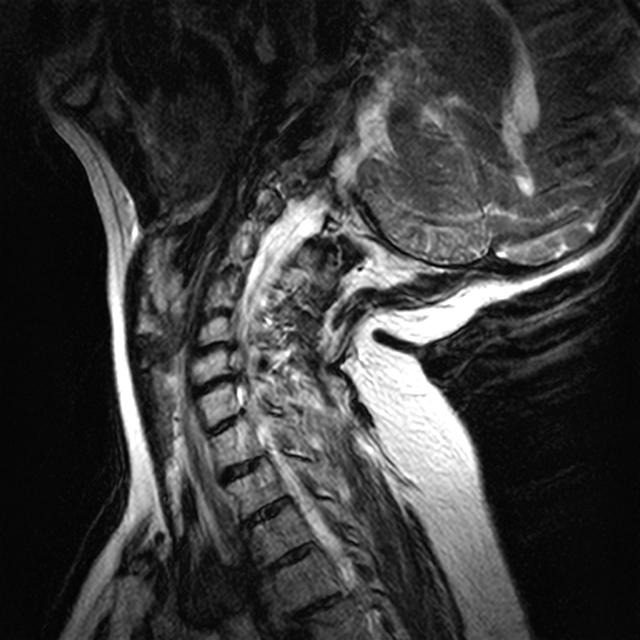

Eine craniocervikale Instabilität (CCI) der Halswirbelsäule, begleitet von Skoliose und fortgeschrittener Arthrose im Nackenbereich.

Durch diese Instabilität kommt es zu schweren Kompressionen im Bereich des Hirnstamms, der Nerven, Blutgefäße und des Liquorraums. Dadurch werden Gehirn, Augen, Herz und Lunge nicht mehr ausreichend mit Sauerstoff, Blut und anderen lebensnotwendigen Substanzen versorgt.

Zusätzlich ist der Fluss der Gehirn-Rückenmarks-Flüssigkeit (Liquor) gestaut, was die neurologischen Symptome weiter verschärft.

Craniocervical instability (CCI) of the cervical spine, accompanied by scoliosis and advanced osteoarthritis in the neck.

This instability causes severe compression of the brainstem, nerves, blood vessels, and the cerebrospinal fluid (CSF) space. As a result, the brain, eyes, heart, and lungs are no longer adequately supplied with oxygen, blood, and other vital substances.

Furthermore, the flow of cerebrospinal fluid is obstructed, which intensifies the neurological symptoms.